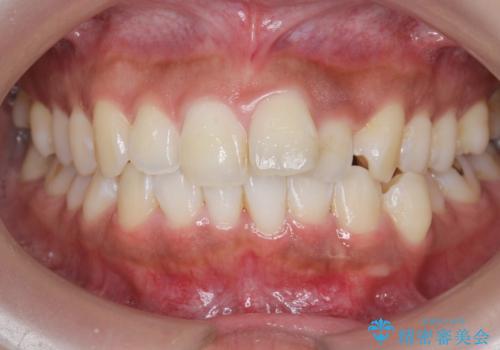

- 前歯のガタつき、突出感のある前歯の改善を求めて来院されました。

前歯の角度を改善し審美性を高めるとともに、奥歯のガタつきも並べ直すことで安定した咬合関係の確立を目指します。

歯列の側方拡大をしっかりと行ったことで歯を抜かずに前歯の角度をしっかりと改善することができました。